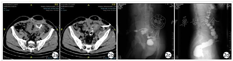

腹部肠碘水造影CT(口服500ml 3%碘海醇溶液)提示:左下腹部脓腔形成,可见引流管与外界相通。

腹部窦道造影提示:经腹部正中窦道口注入造影剂,可见腹部脓腔、乙状结肠及直肠依次显影。经左侧腹部引流管注入造影剂,可见引流管与乙状结肠相通。结肠造影提示:经肛门注入造影剂,可见直肠、乙状结肠及降结肠依次显影,乙状结肠可见造影剂外溢(图2)。